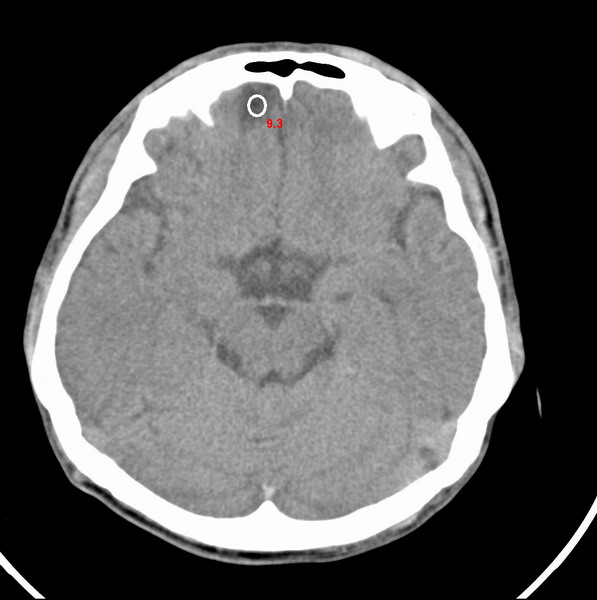

男、29

突发痴呆,失语,记忆减退,反应迟钝二十小时。

右侧额叶低密度影,边界清晰,无占位效应,符合:额叶皮质脑软化灶。

双额叶脑沟增深增宽,皮质性脑萎缩可以考虑么?

左额叶也有类圆形低密度影,同右侧低密度灶近颅底一层同层,病灶周脑实质密度似稍高,成环状,这个没有问题么?

考虑右侧额叶脑软化灶;建议必要时行mri检查排除其他。

考虑皮质软化灶。不考虑胶质瘤,是因为胶质瘤一般发生于白质内。